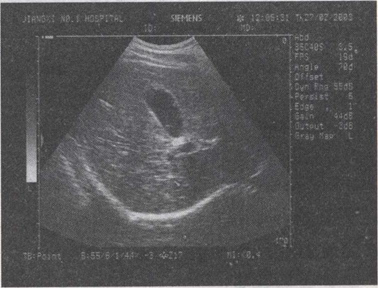

41.女,32岁,偶感右上腹不适多年。声像图如图所示,最可能的诊断为()